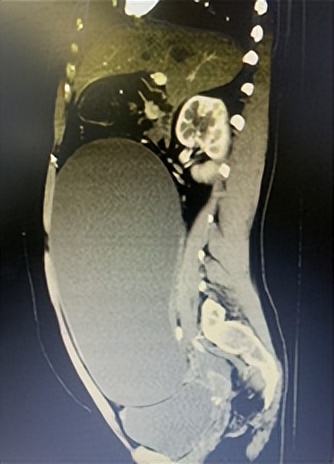

影像下,盆腔巨大囊肿导致患者腹部隆起。

武汉晚报讯(记者魏旭平 通讯员丁群) 26岁的小洁(化名)腹部隆起如怀孕8月大小,导致她误认为自己怀孕。近日,因下腹胀痛不适,小洁(化名)来到武汉市黄陂区人民医院妇科就医,检查发现大肚子实为盆腔巨大囊肿,包块大小达18厘米。